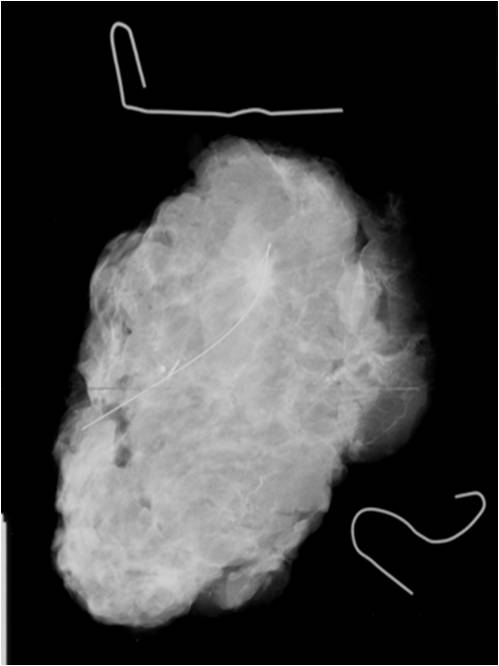

• Preoperative localization: (Picture 10.)

• Indication:

• Small, non-palpable tumor localization might be necessary in order to ensure optimal tissue excision.

• The localization can be made with:

• usually with a steel wire (hook wire or guide wire) localization. Guidance: US or X-ray.

• sometimes with an isotope (technetium-99m labeled nanocolloid). Detection with a scintigraphy probe during surgery (ROLL technique).

• Localization confirmation can be performed with: specimen mammography (=mammogram taken of the removed breast part) (Picture11.)

Image

Picture 10.

Picture 11.